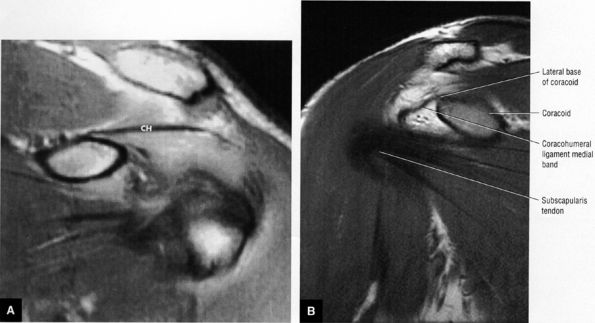

FIGURE 8.87 ● (A) The superior glenohumeral ligament (SGHL) is seen on an enhanced T1-weighted axial image above the level of the coracoid. The extra-articular coracohumeral ligament (CH) and intra-articular SGHL are closely related. The middle portion of the CH crosses the SGHL. The SGHL is oriented perpendicular to the middle glenohumeral ligament (MGL) as shown. BT, biceps tendon; G, glenoid; H, humeral head. (B) Arthroscopic photograph (posterior view) showing the lateral location of the biceps (B) relative to the superior glenohumeral ligament (SGHL). HH, humeral head; Sub, subscapularis tendon.